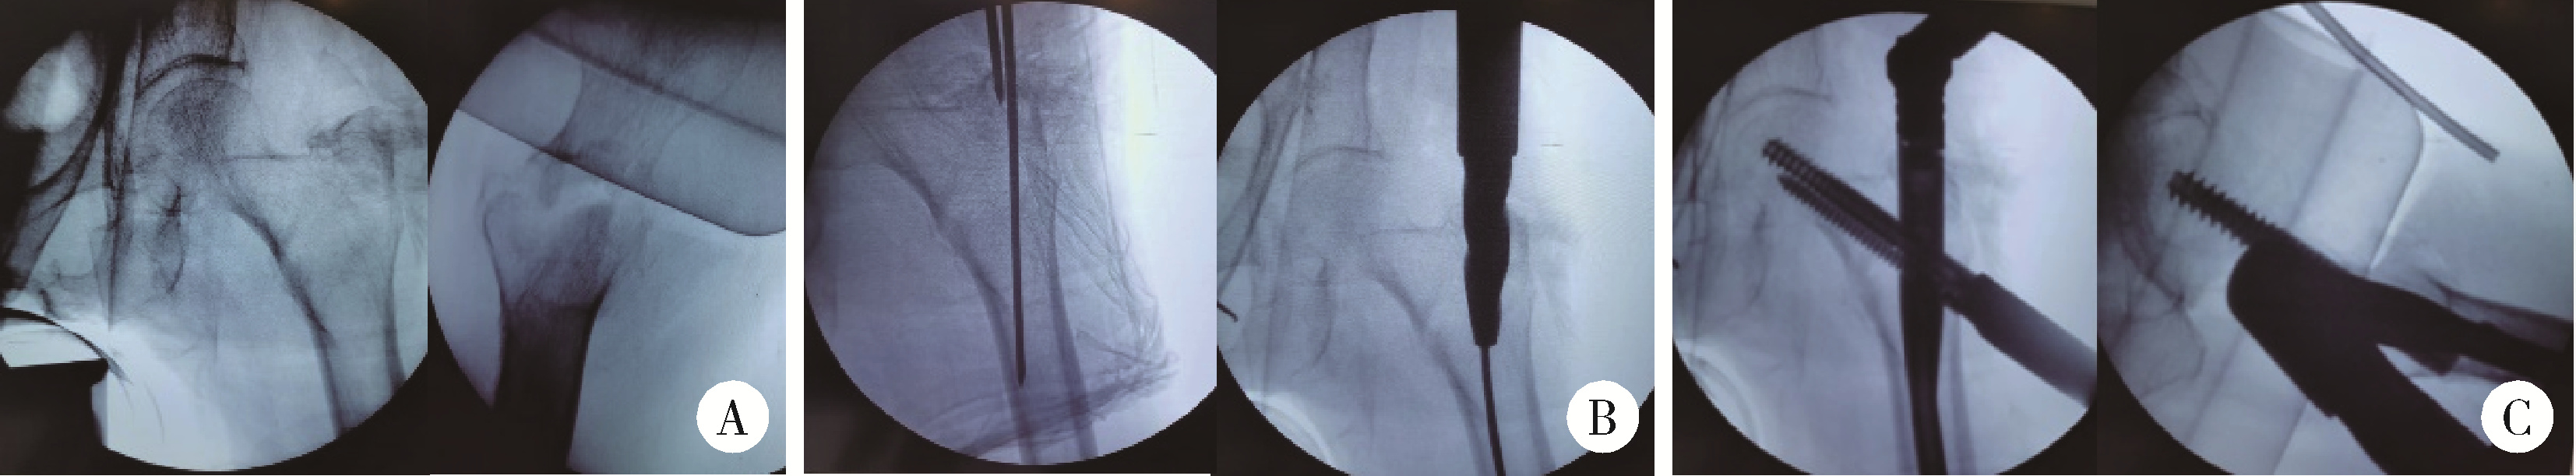

图1 患者第一次入院前髋关节X线片

Figure 1 Hip joint X-ray of patient before initial admission

A, radiographic examinations, including X-ray imaging of anteroposterior view of hips; B, lateral view of left hip, indicate the presence of an intertrochanteric fracture in the left femur.

老年女性患者,88岁,患者2020年10月26日步行时不慎摔倒,左髋着地。于北京大学第一医院急诊查双髋X线片示左侧股骨粗隆间不稳定骨折(图 1)。查体:生命体征平稳。左髋强迫外展外旋位,左下肢短缩约2 cm。左髋局部压痛,轴向叩击痛,活动度拒查。双下肢感觉无异常,双侧足背动脉搏动可。入院后行左股骨粗隆间骨折闭合复位InterTAN髓内钉固定术,术中复位满意,过程顺利(图 2),术后复查髋关节X线片示骨折复位及内固定物位置满意(图 3)。术后次日开始骨化三醇、碳酸钙D3抗骨质疏松治疗,术后1周加用地舒单抗。术后1个半月部分负重,术后3个月可下地行走,无明显不适。2021年10月7日(术后12个月)无明显诱因出现左髋疼痛,进行性加重,逐渐出现行走困难。2022年2月28日(术后16个月)于北京大学第一医院门诊复查双髋正位X线片考虑左侧股骨颈骨折,内固定物对髋臼侧骨质有一定破坏(图 4),为行治疗收治入院。既往有高血压、腔隙性脑梗、房颤病史。查体:生命体征平稳,左髋关节周围压痛明显,无红肿,关节活动受限,疼痛明显,查体配合差。入院查血常规:白细胞计数7.1×109/L,中性粒细胞计数6.5×109/L,中性粒细胞百分比92.3%,超敏C反应蛋白4.27 mg/L,降钙素原0.02 μg/L,除外感染后行左髋关节内固定物取出加半髋关节置换术,术中未见浑浊关节液及组织液,既往股骨粗隆间骨折部位已完全愈合,新发股骨颈骨折(图 5),髋臼外上方有一处头颈螺钉切割出的缺损区,直径约1.5 cm,内有纤维瘢痕组织填充,取局部组织留取病理,送咽拭子细菌培养,培养结果阴性。术中采用骨水泥型11号股骨假体柄(长度200 mm)和外径44 mm的双极金属股骨头行半髋关节置换术,术后复查髋关节X线片(图 6),可见髋臼侧骨质密度减低。术后预防性抗感染治疗,术后1周出院,院外继续抗骨质疏松治疗。术后3个月患者反馈左髋疼痛及功能明显改善,患者及家属对治疗满意。